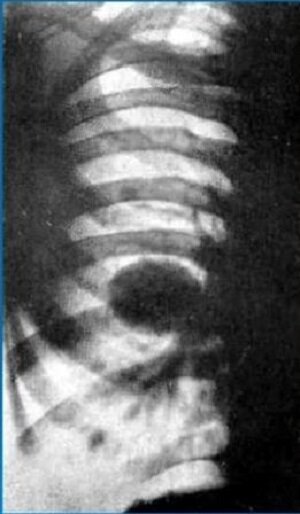

Опухолевый узел сохраняет шаровидную форму и бугристые контуры (рис. 3.4, а, б).

-5